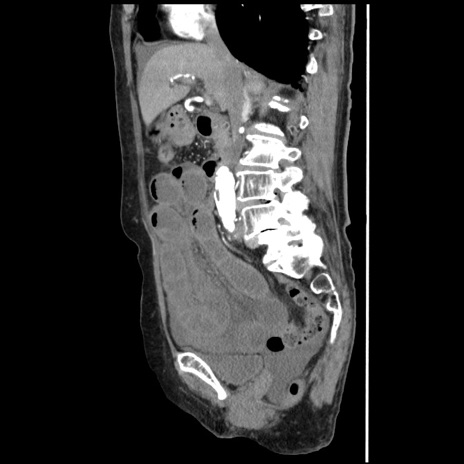

症例1(矢状断像)

【症例】80歳代女性

【主訴】腹痛

【現病歴】8時間前から腹痛あり来院。

【既往歴】糖尿病、脂質異常症、子宮体癌にて子宮全摘術

【身体所見】意識清明・会話良好だが腹痛で苦悶様、全腹部にわたって反跳痛と圧痛あり

【データ】WBC 13600、CRP 0.14、LDH 224、CK 90